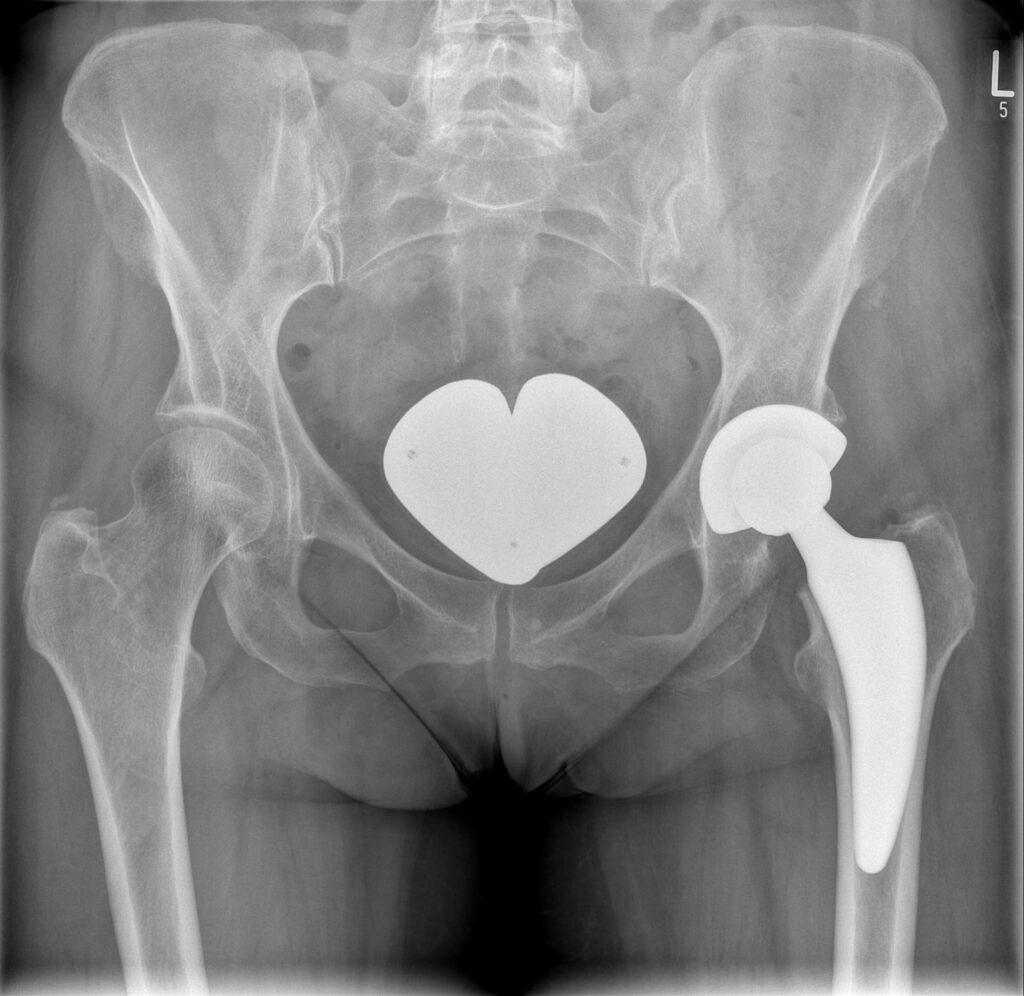

Hüftgelenk

Der künstliche Hüftgelenksersatz (HTEP) ist die weltweit am häufigsten vorgenommene endoprothetische Operation. Dieses OP-Verfahren können wir Ihnen im Rahmen unseres innovativen ORTHOPAEDICON FAST TRACK Konzeptes im Krankenhaus Spremberg ambulant anbieten. Alle Patienten, für die eine ambulante Versorgung nicht geeignet ist, versorgen wir ebenfalls dort: nach ERAS Kriterien, mit modernsten Implantaten und einer strukturierten Vor- und Nachbetreuung.

Grundsätzlich unterscheidet man zementierte – also mit einem Spezialkleber im Knochen befestigte – und zementfreie Prothesensysteme. Beide Arten der Verankerung sind prinzipiell gleichwertig, es muss individuell entschieden werden, welches Endoprothesenmodell für den Patienten am besten geeignet scheint.

Zementfreie HTEP werden überwiegend bei jüngeren Patienten eingesetzt. Hier gibt es wiederum verschiedene Prothesensysteme, die sich in der Höhe der Krafteinleitung unterscheiden: klassische, über Jahrzehnte bewährte Schaftprothesen, z.B. TAPERLOC, und neuere Modelle mit weniger Knochenverlust (Kurzschaftprothesen, z.B. Fitmore), für die es ermutigende mittelfristige Ergebnisse gibt und die für minimalinvasive Zugänge besser geeignet sind.

Entscheidend für die Haltbarkeit einer Endoprothese ist neben der korrekten Positionierung der Komponenten die Materialauswahl der eigentlichen Gleitpaarung zwischen Kopf und Pfanne.

Für den auf dem Prothesenschaft fixierten Kopf kommt eine BIOLOX delta ® Hochleistungskeramik zum Einsatz,  für das Gleitlager in der Gelenkpfanne verwenden wir in der Regel ein extrem abriebarmes hochvernetztes Polyethylen (UHMWPE) zum Einsatz: DURASUL ®. Für junge, aktive Patienten kann auch eine reine keramische Gleitpaarung von Vorteil sein.